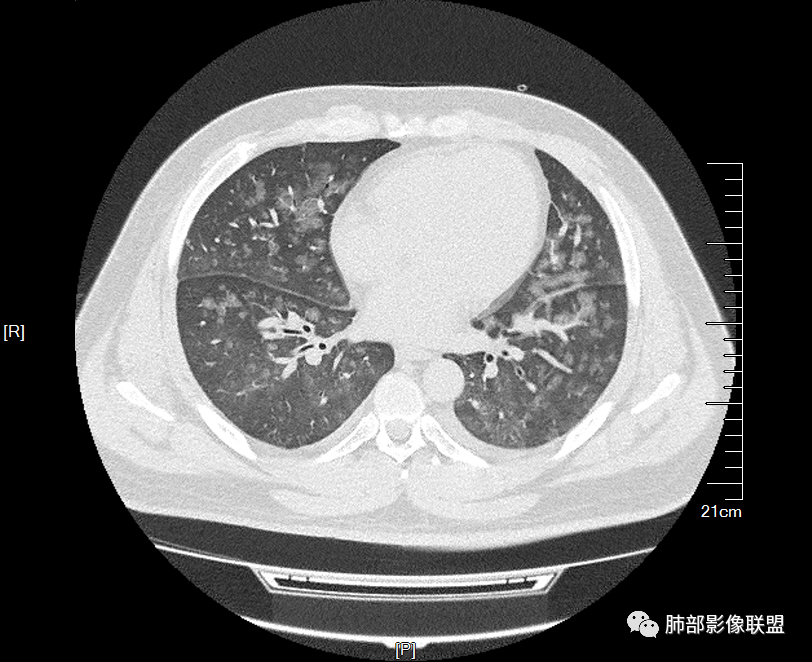

双肺多发弥漫性磨玻璃结节影,大小不一,形态不规则,部分融合,支气管未见明显扩张,部分血管束略增粗,叶裂胸膜增厚,临床有痛风,左足痛6天,考虑:1:痛风结节(一般实性结节,很少磨玻璃结节影)2:血管炎?3:病毒性肺炎(水痘-疱疹肺炎?)

双肺多发腺泡结节及磨玻璃,小叶间隔增厚(大网格状),腺泡结节内及磨玻璃内可见细网格影(小叶内间隔增厚),影像表现符合肺泡出血改变,血肌酐升高,考虑肺肾综合征。鉴别肺水肿。

两肺弥漫向心分布的腺泡结节,部分融合,两肺小叶间隔增厚,血肌肝高,考虑肺泡性肺水肿

年轻男性,既往血肌酐升高,左足痛六天入院,有痛风及高血压病史。CT示双肺多发磨玻璃结节影,不规则,部分融合成团或片状,小叶间隔增厚,以双下肺为明显,叶间胸膜亦见增厚。考虑为1.Good-Pasture综合征。2.病毒性肺炎?3.肺水肿?

年轻男性,痛风史,高血压史,肌酐高,左足痛6天入院。胸CT:双肺多发弥漫性磨玻璃结节影,大小不一,部分融合,上中下肺都有,中内带多,胸膜下少。部分血管束略增粗,小叶内间隔、小叶间隔增厚,下肺明显,左室大。叶裂胸膜增厚。临床有痛风,左足痛6天,考虑:心衰、间质性肺水肿?弥漫性肺泡出血?鉴别:MPA,肺肾综合征,痛风结节等。

32岁男性,左足痛入院。有痛风、肌酐升高、高血压病史。CT:两肺弥漫磨玻璃结节,小叶间隔增厚、小叶内间质增厚,两侧少量胸水。考虑:1.肺水肿;2.过敏性肺炎;3.肿瘤?

多发GGO结节,边界清,以全小叶、小叶中心为主:

GGO背景

小叶间隔增厚,无明显重力趋势

中轴间质稍增厚

细网格也明显

中轴间质增厚,小叶间隔增厚,小叶内间质增厚,部分重力作用,双侧对称,胸水,按理淋巴道回流受阻有

肺水肿类病变有

问题是腺泡结节如何解释?